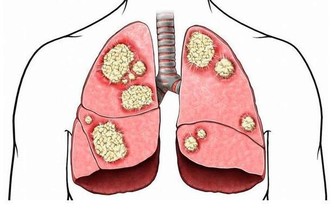

·呼吸不暢;